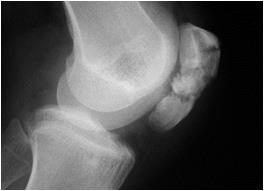

Рентгенография. Во многих случаях диагностика переломов надколенника не представляет трудностей благодаря наглядному симптомо-комплексу

Переломы без смещения, сопровождающиеся более скудной клинической картиной, не вызывают сложностей благодаря вовремя выполненного стандартного рентгенологического обследования (рис. 53).

Рис. 53. Рентгенограммы переломов надколенника.